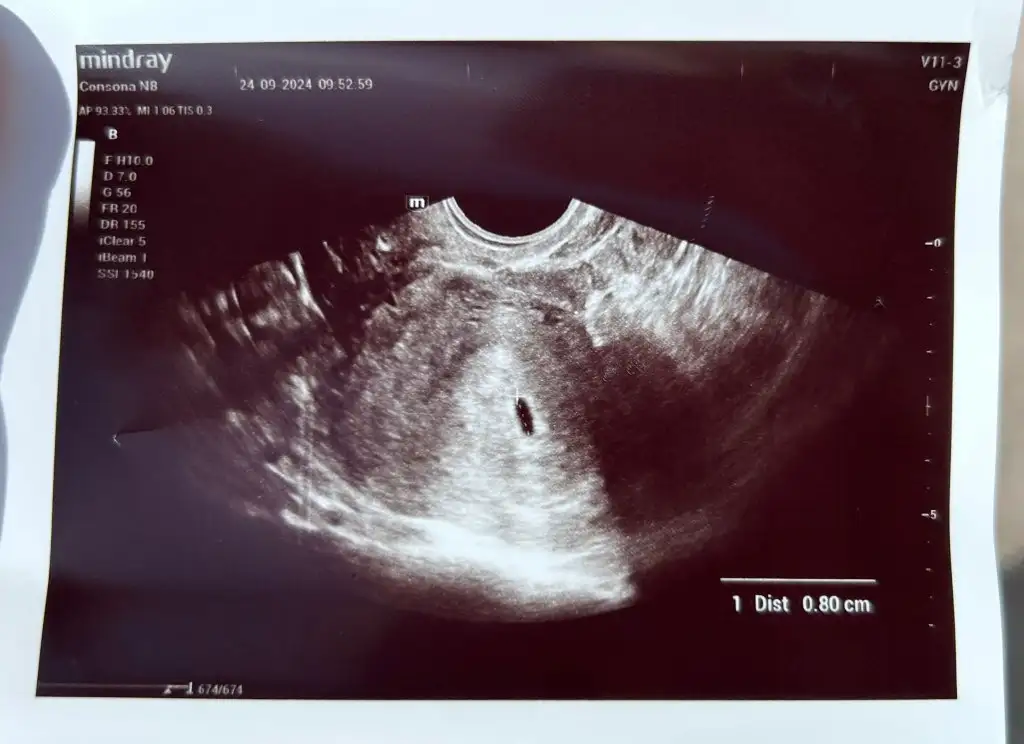

Kızlar selam :KK200: 5+0'dayım bugün, 6. haftaya girdim. Keseyi görmeye doktora gittim bu sabah ama karından göremedi vajinal olarak gördü, 8mm kese dedi. Yolk sac'a dair bilgi vermedi, sormamışım ben de heyecandan. Betama bugün bakmadı ama en son cuma verdiğim değere göre bugün 1600 lerde olması gerekiyor. Sanırım ben geç yumurtladığım için geç döllenme bebeğim. 4,5-5 haftalık dedi doktor çünkü. Sizce endişe edecek bir durum var mı? Daha önce tam bu haftalarda düşük yaptığım için gelişmez ve düşer diye çok korkuyorum

Eklentiler

• WhatsApp Image 2024-09-24 at 10.17.42.webp

WhatsApp Image 2024-09-24 at 10.17.42.webp

29,8 KB · Görüntüleme: 57